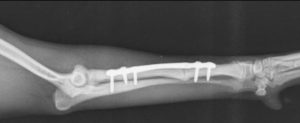

În cazul raselor de talie foarte mică, cunoscute drept “toy breeds”, fracturile de radius și ulnă constituie o categorie aparte de traumatisme ortopedice. Vascularizația redusă la acest nivel face ca aceste oase să fie vulnerabile chiar și în urma unor accidente minore – o săritură din brațele proprietarului sau de pe mobilier poate fi suficientă pentru a produce o fractură completă.

Tratamentul acestor leziuni este delicat, deoarece diametrul osos este extrem de redus, iar stabilizarea trebuie realizată cu maximă precizie. În prezent, dispunem de implanturi ortopedice de ultimă generație, concepute special pentru pacienții sub 2 kg, care permit stabilizarea sigură și eficientă a oricărui tip de fractură.

Pentru aceste rase, un pas esențial în managementul postoperator îl reprezintă extragerea implanturilor după confirmarea radiologică a vindecării osoase. Eliminarea acestora reduce riscul de resorbție osoasă și contribuie la menținerea unei integrității structurale optime pe termen lung.

Intervențiile sunt realizate cu anestezie inhalatorie și tehnici de blocaj loco-regional, ceea ce diminuează semnificativ nivelul de durere resimțită de pacient atât în timpul intervenției, cât și postoperator.

Astfel de situații demonstrează cât de mult contează echipamentele adecvate, experiența echipei și un protocol bine stabilit pentru a obține o recuperare completă și sigură.